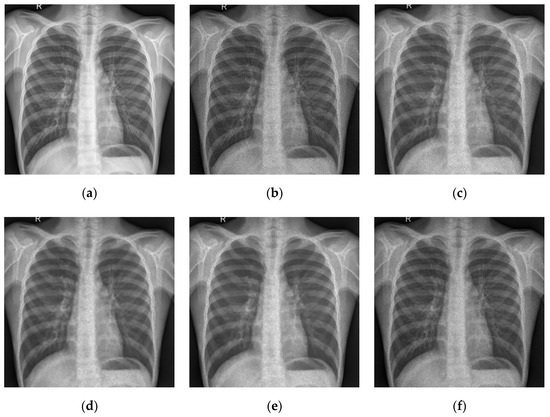

5.2. Numerical Simulations on Medical Images

5.2.2. Different Methods

- ADMM Method

5.2.3. Comparison with Other Variational Models